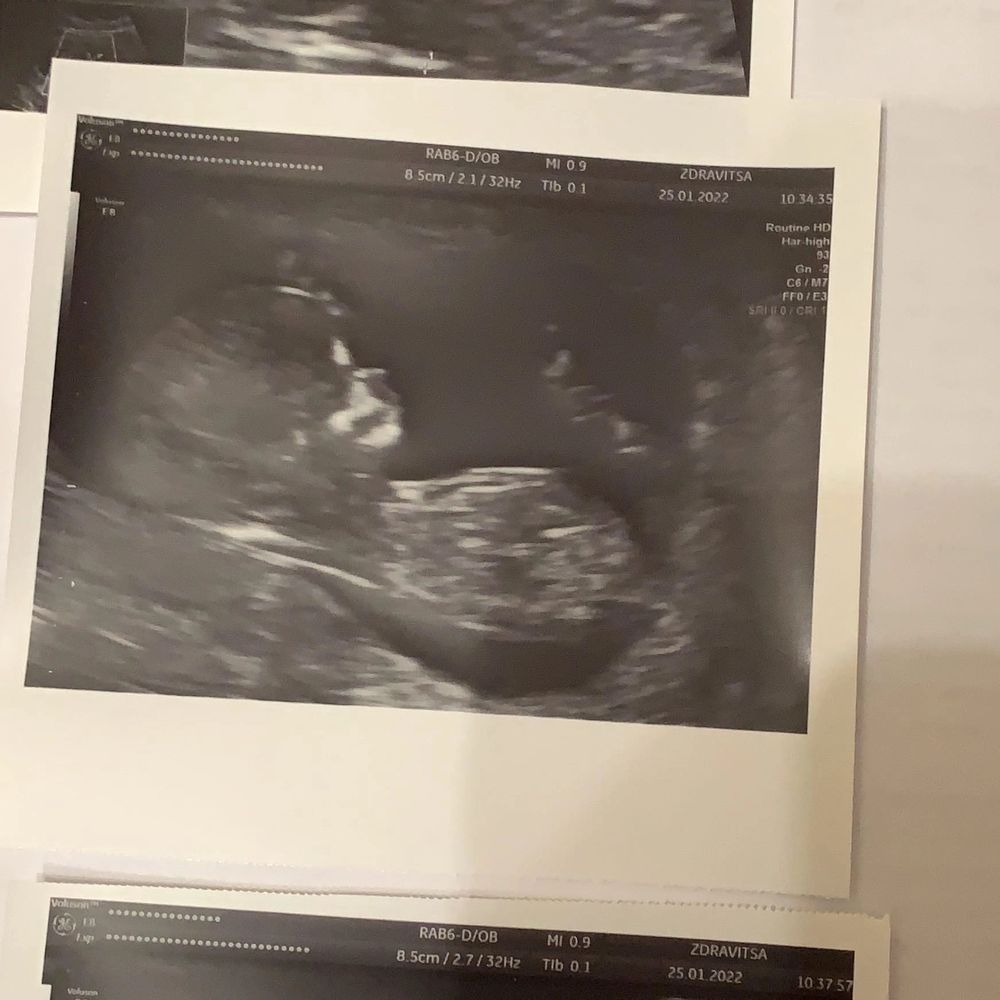

14 н. 4 д. Приключения продолжаются🌸 Мне поставили диагноз🙈